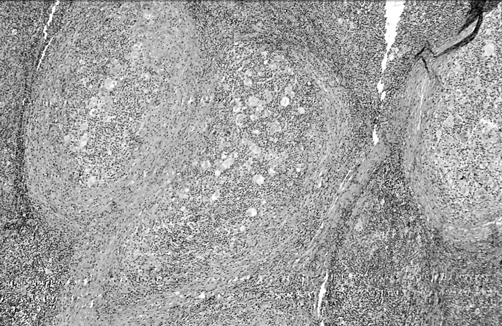

1) с нодулярным (узловатым) склерозом (рис. 1);

Рисунок 1. Лимфома Ходжкина. Вариант: нодулярный склероз

2) смешанно-клеточный (рис. 2);

Рисунок 2. Лимфома Ходжкина. Вариант: смешанно-клеточный

В свою очередь, вариант с нодулярным склерозом подразделяется на два типа в зависимости от клеточного состава “нодулей”: тип I — со смешанно-клеточным составом нодулей и тип II — с лимфоидным истощением в них.

Вариант с нодулярным склерозом чаще встречается у молодых больных, среди которых преобладают женщины. При этом варианте больше ранних стадий с поражением лимфатических узлов только выше диафрагмы. Своеобразие архитектоники опухолевой ткани обусловлено наличием тяжей коллагена, делящих узел на участки округлой формы — нодули.

Смешанно-клеточный вариант встречается преимущественно у больных старшей возрастной группы. Этот вариант имеет классическую морфологическую картину, когда рисунок строения лимфатического узла стерт, а клетки Ходжкина и опухолевые клетки Березовского — Рид — Штернберга редко разбросаны среди лимфоцитов, эозинофилов, гистиоцитов и др.